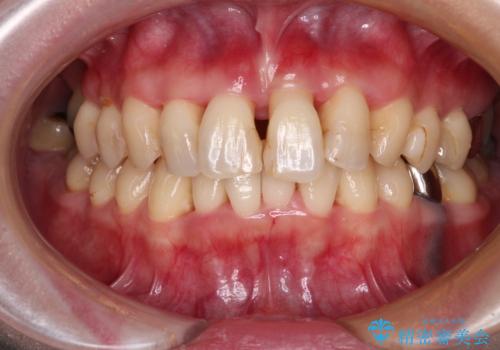

受け口と八重歯を改善 インビザライン矯正治療